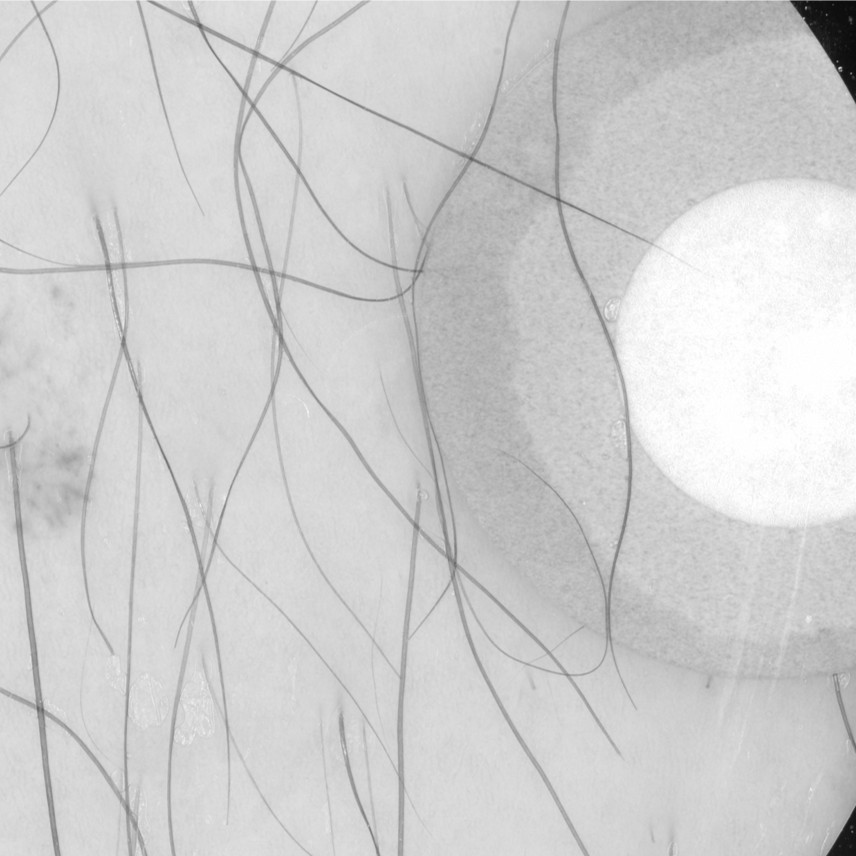

Raw Data 𝒟={(xi,yi)}i=1N\mathcal{D}=\{(x_{i},y_{i})\}_{i=1}^{N}caligraphic_D = { ( italic_x start_POSTSUBSCRIPT italic_i end_POSTSUBSCRIPT , italic_y start_POSTSUBSCRIPT italic_i end_POSTSUBSCRIPT ) } start_POSTSUBSCRIPT italic_i = 1 end_POSTSUBSCRIPT start_POSTSUPERSCRIPT italic_N end_POSTSUPERSCRIPT Refer to captionRefer to captionRefer to captionRefer to captionRefer to captionRefer to captionRefer to caption Edge-enhanced E(xi)E(x_{i})italic_E ( italic_x start_POSTSUBSCRIPT italic_i end_POSTSUBSCRIPT ) Refer to caption Refer to caption Refer to caption Refer to caption Refer to caption Refer to caption Refer to caption Extract ϕ(xi)\phi(x_{i})italic_ϕ ( italic_x start_POSTSUBSCRIPT italic_i end_POSTSUBSCRIPT )Train fθf_{\theta}italic_f start_POSTSUBSCRIPT italic_θ end_POSTSUBSCRIPTon {(xi,yi)}i=1N\{(x_{i},y_{i})\}^{N}_{i=1}{ ( italic_x start_POSTSUBSCRIPT italic_i end_POSTSUBSCRIPT , italic_y start_POSTSUBSCRIPT italic_i end_POSTSUBSCRIPT ) } start_POSTSUPERSCRIPT italic_N end_POSTSUPERSCRIPT start_POSTSUBSCRIPT italic_i = 1 end_POSTSUBSCRIPTTrain fθf^{\star}_{\theta}italic_f start_POSTSUPERSCRIPT ⋆ end_POSTSUPERSCRIPT start_POSTSUBSCRIPT italic_θ end_POSTSUBSCRIPTon {(E(xi),yi)}i=1N\{(E(x_{i}),y_{i})\}^{N}_{i=1}{ ( italic_E ( italic_x start_POSTSUBSCRIPT italic_i end_POSTSUBSCRIPT ) , italic_y start_POSTSUBSCRIPT italic_i end_POSTSUBSCRIPT ) } start_POSTSUPERSCRIPT italic_N end_POSTSUPERSCRIPT start_POSTSUBSCRIPT italic_i = 1 end_POSTSUBSCRIPTFine-tune fθf_{\theta}italic_f start_POSTSUBSCRIPT italic_θ end_POSTSUBSCRIPT on modality data 𝒟mod\mathcal{D}^{mod}caligraphic_D start_POSTSUPERSCRIPT italic_m italic_o italic_d end_POSTSUPERSCRIPTFine-tune fθf^{\star}_{\theta}italic_f start_POSTSUPERSCRIPT ⋆ end_POSTSUPERSCRIPT start_POSTSUBSCRIPT italic_θ end_POSTSUBSCRIPT on modality data 𝒟mod\mathcal{D}^{mod}caligraphic_D start_POSTSUPERSCRIPT italic_m italic_o italic_d end_POSTSUPERSCRIPTCompare perf. δi=𝕀[fθ>fθ]\delta_{i}=\mathbb{I}[f^{\star}_{\theta}>f_{\theta}]italic_δ start_POSTSUBSCRIPT italic_i end_POSTSUBSCRIPT = blackboard_I [ italic_f start_POSTSUPERSCRIPT ⋆ end_POSTSUPERSCRIPT start_POSTSUBSCRIPT italic_θ end_POSTSUBSCRIPT > italic_f start_POSTSUBSCRIPT italic_θ end_POSTSUBSCRIPT ]Map meta-classifier m(ϕ(xi))δim(\phi(x_{i}))\rightarrow{}\delta_{i}italic_m ( italic_ϕ ( italic_x start_POSTSUBSCRIPT italic_i end_POSTSUBSCRIPT ) ) → italic_δ start_POSTSUBSCRIPT italic_i end_POSTSUBSCRIPTGeneral pre-training Modality-specific fine-tuning

(a) Training: Our approach to pre-training, modality-specific fine-tuning, and meta-classifier mapping.

Figure 1: Our approach: (a) training pipeline and (b) inference pipeline.